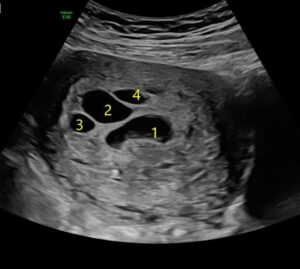

The 8 weeks wait until the first ultrasound was the longest wait of my life. When I lay on the bed, alone once again, I held my breath. I thought, ‘Please let there be a heartbeat and healthy baby this time,’ and there was! I saw a cute and strong flicker of the heartbeat. But, that wasn’t all I saw. There were multiple black circles surrounding the baby. I kept staring at the screen and asked the ultrasound technician, ‘What are those?’ My heart dropped when she said the words, ‘I don’t know.’ I thought, ‘Please don’t let me lose this baby, I can’t do this again, not again, no!’ The ultrasound technician kept scanning. She said, ‘Did you take any fertility drugs to get pregnant?’ ‘No?’ I responded while extremely confused. ‘Well this could be multiple pregnancies but I don’t see the other babies yet, just their sacs.’ I asked her how many sacs she could see. She said there were 6 sacs plus a baby. I was shocked.

My OBGYN was very confused as she reviewed the ultrasound. She said, ‘I don’t know if this pregnancy is viable.’ She sent me to a high-risk doctor who had been seeing patients with high-risk pregnancies for over 40 years. He reviewed my ultrasound and was puzzled. He said, ‘I have seen cases with maybe two other sacs but never 6,’ and told me he didn’t know what they were but had a feeling they would go away. All we could do was wait.

At 36 weeks pregnant, I delivered a healthy baby girl named Ella. She was 5 pounds 6 ounces and sweet as could be. My high-risk doctor came to visit me in the delivery room. He told me to print out my ultrasound and hung it in his office for months. We still don’t know why or what they were. Were they 6 other babies? Were they cysts? Were they something that formed to protect the baby? I like to think they were her guardian angels making sure I didn’t lose another baby.